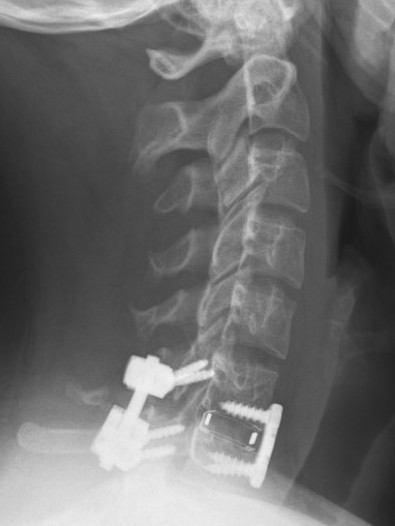

Xray / CT

Large antero-inferior body fragment / tear drop

- > 20 %

- stays attached to ALL

+/- posterior superior fragment retropulsed into canal

Urgent reduction

- tongs

- GA

Anterior +/- posterior fixation